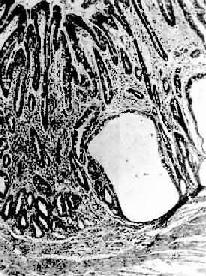

慢性萎缩性胃炎

图10-3 慢性萎缩性胃炎

幽门腺大部分萎缩消失,胃小凹延长,有潴留性小囊形成,腺上皮中杂有不少杯状细胞(肠上皮化生),固有膜内有不少慢性炎性细胞浸润(Ⅱ74-4950)